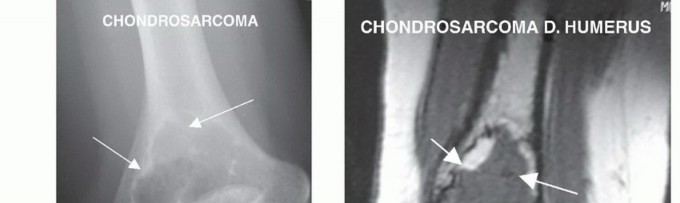

الساركوما هي نوع من السرطان ينشأ في الأنسجة الرخوة أو العظام. على الرغم من أنها نادرة في الجزء البعيد من عظم العضد، إلا أنها قد تحدث. تشمل الأنواع الشائعة:

- الساركوما الغضروفية (Chondrosarcoma): تنشأ من الخلايا المنتجة للغضاريف.

الأشعة السينية العادية

- الغرض: هي الخطوة الأولى لتحديد موقع الورم في العظم، وتقدير حجمه الأولي، وتكوين تشخيص تفريقي.

- ما تظهره: يمكن أن تكشف عن التغيرات في بنية العظم، مثل التدمير العظمي، أو تكوين عظم جديد غير طبيعي (التكلس)، أو الكسور المرضية. بعد العلاج الكيميائي، يمكن استخدامها لتقييم استجابة الورم للعلاج.

الرنين المغناطيسي

- الغرض: هو الأكثر دقة لتحديد مدى انتشار الورم داخل وخارج العظم (intra- and extraosseous extent)، وكذلك للكشف عن النقائل القافزة (skip metastases).

- ما يظهره: يوفر صورًا مفصلة للأنسجة الرخوة، مما يساعد في تقييم قرب الورم من الأوعية الدموية الرئيسية (الشريان العضدي) والأعصاب (المتوسط، الزندي، الكعبري). يعتبر حاسمًا للتخطيط الجراحي وتحديد طول الجزء العظمي الذي سيتم استئصاله.